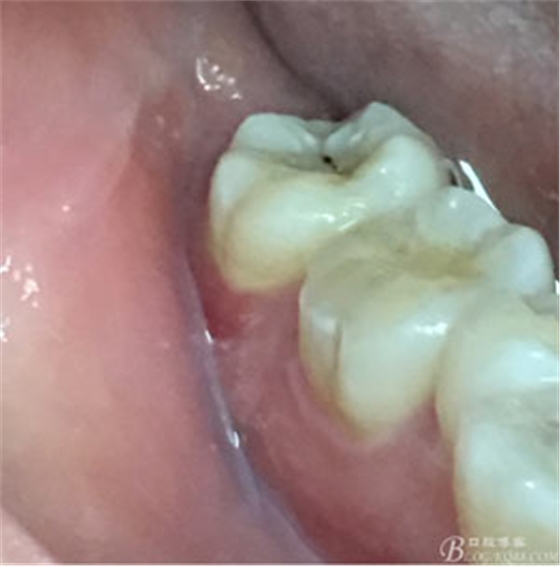

圖2.37牙冠基本完好,松動(dòng)Ⅰ度。合面有一開(kāi)髓孔被棉球覆蓋,頰側(cè)牙齦輕度紅腫。

圖3.取出棉球口內(nèi)發(fā)現(xiàn)37合面有開(kāi)髓孔,探針出血,頰側(cè)牙齦紅腫